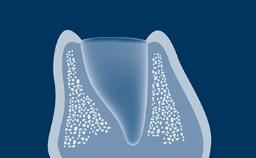

The periosteal releasing incision, or PRI, is a common oral surgical technique that is undertaken to increase the mobility of a surgical flap.

When performed correctly, the periosteal releasing incision allows the flap to be coronally advanced so that tension-free primary closure of the surgical site can be achieved.